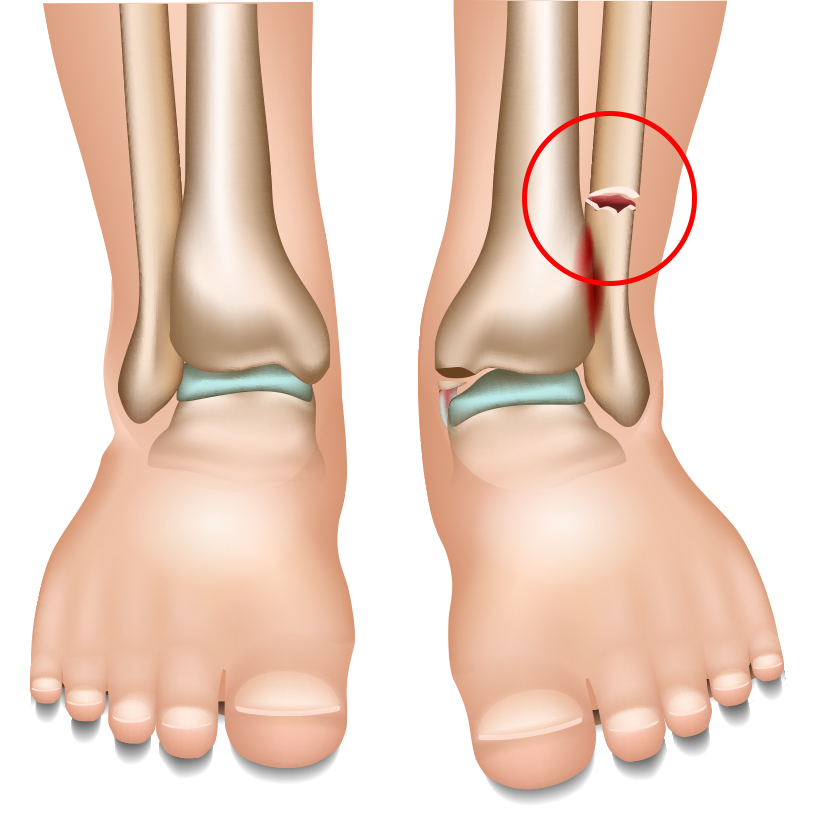

심한 외상으로 발생하는

발/발목 골절

외상에 인해 발 또는 발목의 뼈가 부러져 부종과 통증을 유발하는 발/발목 골절은 적기에 치료하지 않으면

인대, 신경, 혈관 손상을 물론 관절염으로 이어질 수 있기 때문에 ‘빠른 치료’가 무엇보다 중요합니다.